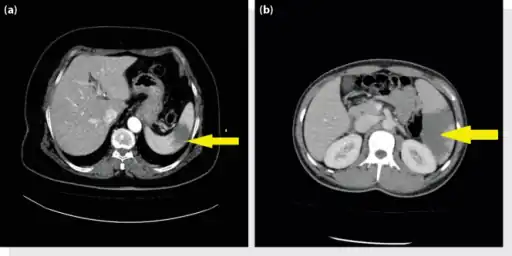

a, b) Splenic infarction.

Splenic infarct seen on CT

An abdominal CT scan is the most commonly used modality to confirm the diagnosis,[3] although abdominal ultrasound can also contribute.[16][17][18]